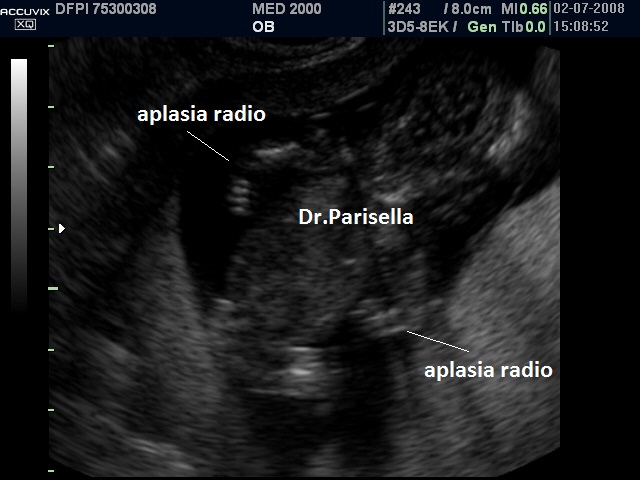

E' una sindrome malformativa congenita caratterizzata da aplasia bilaterale del radio con presenza dei pollici e trombocitopenia.

A differenza di altre malattie associate ad aplasia del radio, nella TAR vi è un segno clinico caratteristico: i pollici sono presenti.